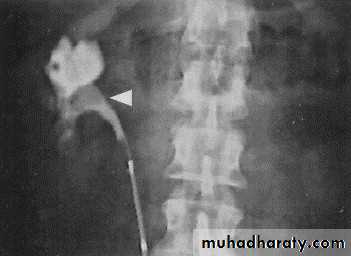

Retrocaval ureter:- (right ureter ) behind inferior vena cava.

*PUJ obstruction&retrocaval ureter